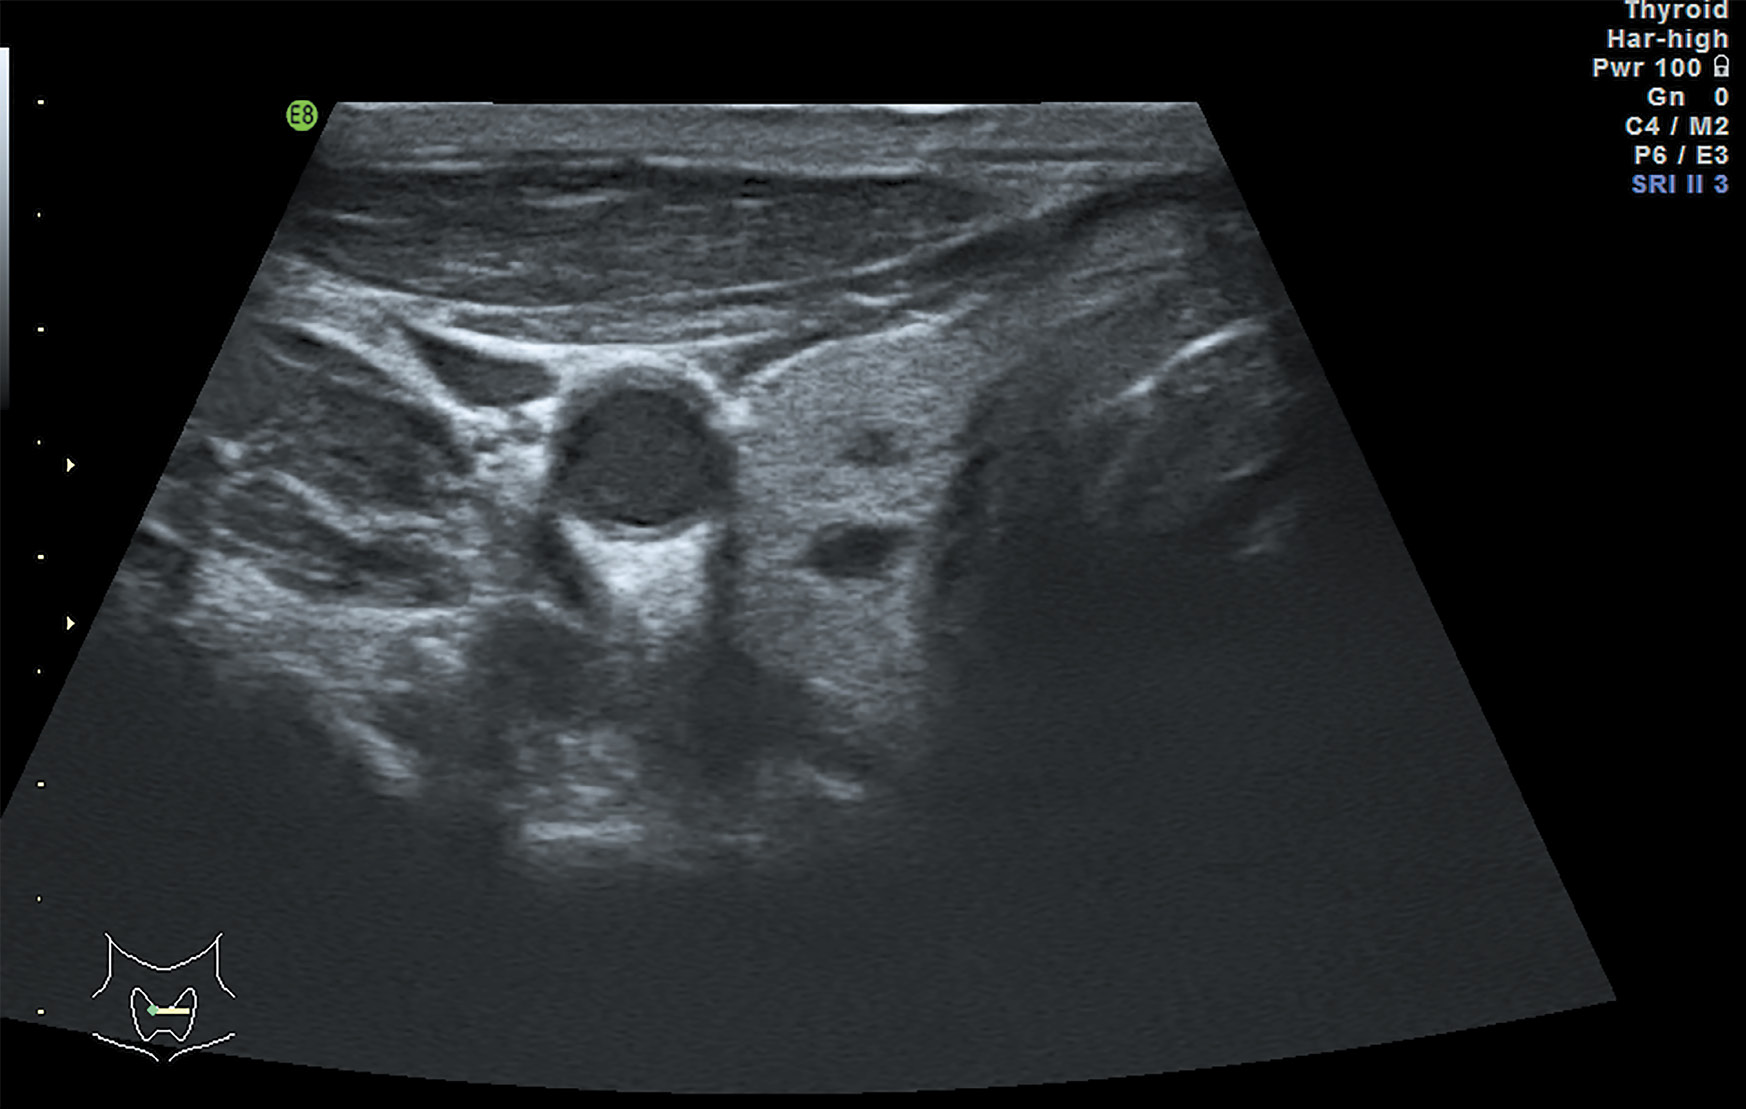

1. Рисунок 1. Ультразвуковое изображение щитовидной железы. | |